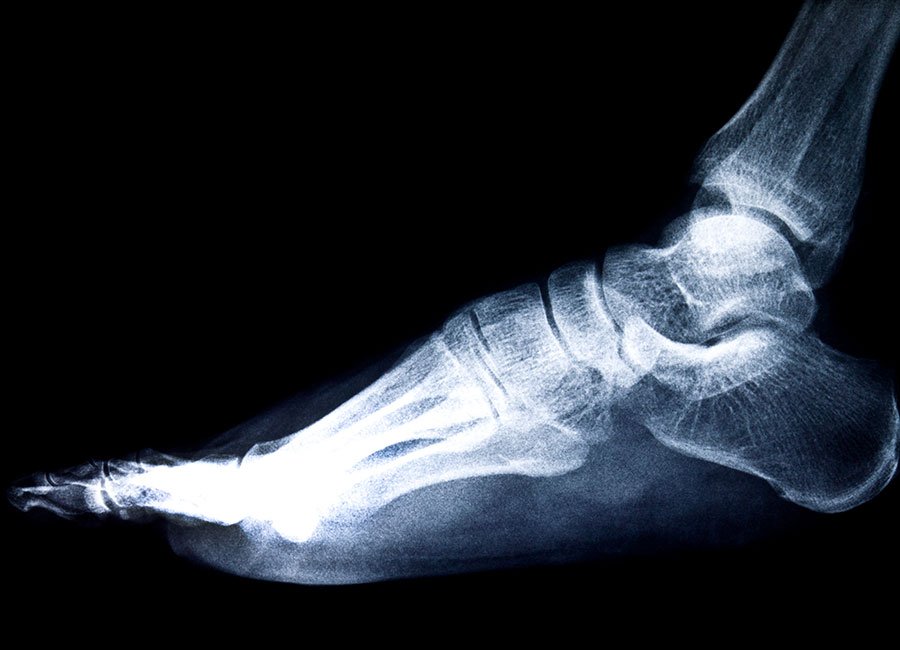

Chirurgia del piede

Correzione delle principali deformità e patologie del piede, con interventi chirurgici mirati a migliorare l’equilibrio biomeccanico e la qualità della deambulazione di ogni individuo.